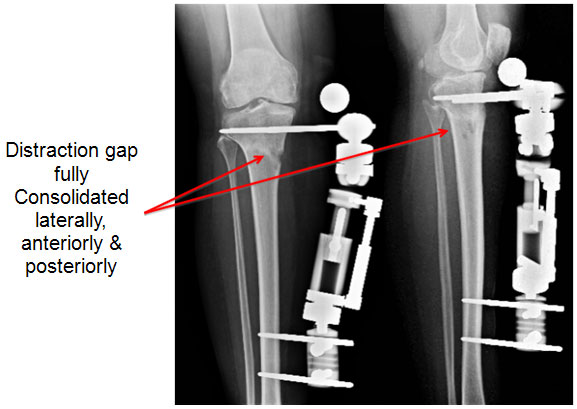

| 12 weeks post surgery – just before fixator removal |

| 12 weeks post surgery the distraction gap is consolidated well and osteotomy is healed. Even though a slight gap is seen on the medial cortex (inner border on the left picture), other 3 sides have healed well and patient is walking comfortably bearing full weight. |